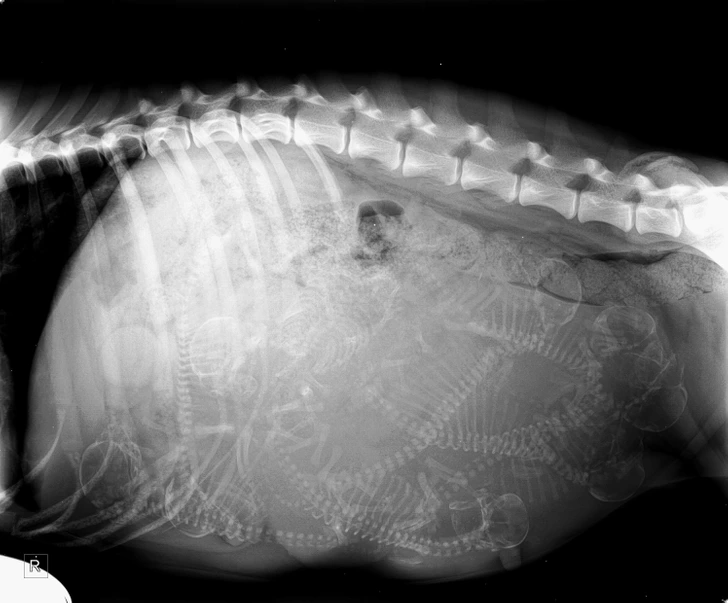

#5 RTG sestrinej sučky, na ktorom vidno jej šteniatka